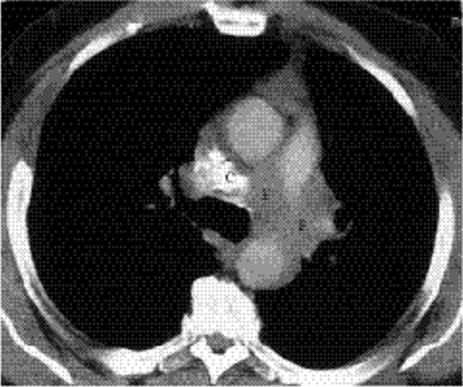

Contrast-enhanced CT may show a characteristic appearance in mediastinal tuberculous lymphadenitis, with central nodal low attenuation (Fig. 5.26) and peripheral enhancement. This appearance also occurs with atypical mycobacterial infections, lymphoma, metastases, and Whipple disease. CT is more sensitive for detection of calcification.

Figure 5.26 Primary tuberculosis. Computed tomography demonstrates low attenuation of a subcarinal lymph node (arrow).